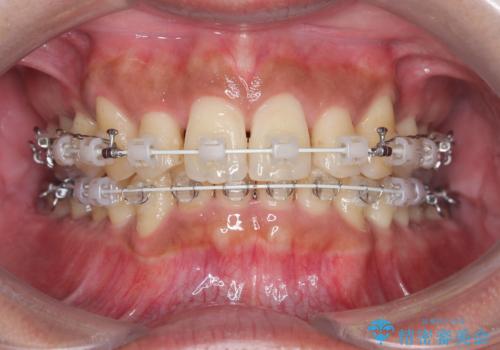

今回の矯正治療では、まず歯が並ぶスペースを確保するため、上顎の小臼歯を抜歯しました。抜歯によってできたスペースを利用して前歯を奥へ移動させ、デコボコを解消。同時に、奥歯の咬み合わせを調整することで、深すぎた咬み合わせであるディープバイトも改善しました。治療の結果、長年気にされていた前歯のデコボコが解消され、理想的な歯並びに。さらに、正しい咬み合わせを獲得したことで、機能的にも安定した美しい口元になりました。